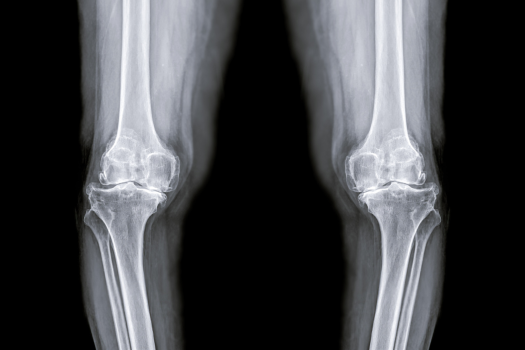

変形性膝関節症の診断と区別

変形性膝関節症の診断には、レントゲン検査が不可欠です。

初期症状として膝の腫れや正座困難が現れ、特に長時間の安静後に歩き始める際に大きく痛みを感じます。

この病気はO脚の方に多く、筋力低下も症状を悪化させる要因となります。また、半月板損傷を伴うことも少なくないため、適切な検査で変形の程度を正確に診断することが、効果的な対処法への第一歩です。